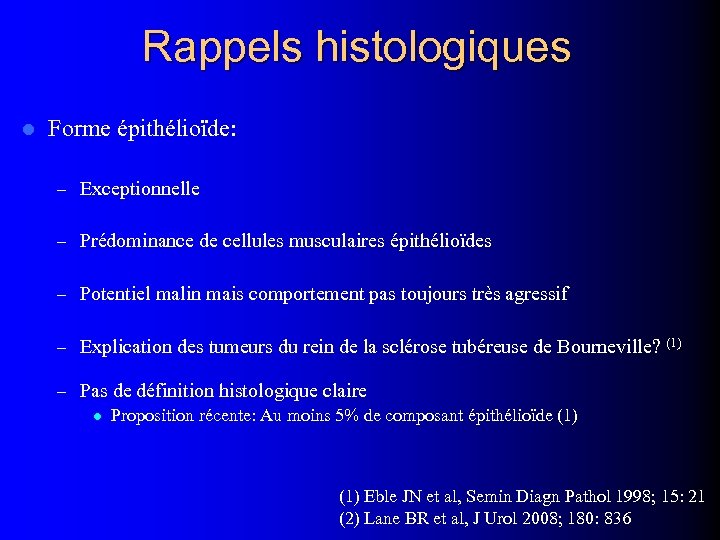

Rappels histologiques l Forme épithélioïde: – Exceptionnelle – Prédominance de cellules musculaires épithélioïdes – Potentiel malin mais comportement pas toujours très agressif – Explication des tumeurs du rein de la sclérose tubéreuse de Bourneville? (1) – Pas de définition histologique claire l Proposition récente: Au moins 5% de composant épithélioïde (1) Eble JN et al, Semin Diagn Pathol 1998; 15: 21 (2) Lane BR et al, J Urol 2008; 180: 836

Rappels histologiques l Forme épithélioïde: – Exceptionnelle – Prédominance de cellules musculaires épithélioïdes – Potentiel malin mais comportement pas toujours très agressif – Explication des tumeurs du rein de la sclérose tubéreuse de Bourneville? (1) – Pas de définition histologique claire l Proposition récente: Au moins 5% de composant épithélioïde (1) Eble JN et al, Semin Diagn Pathol 1998; 15: 21 (2) Lane BR et al, J Urol 2008; 180: 836